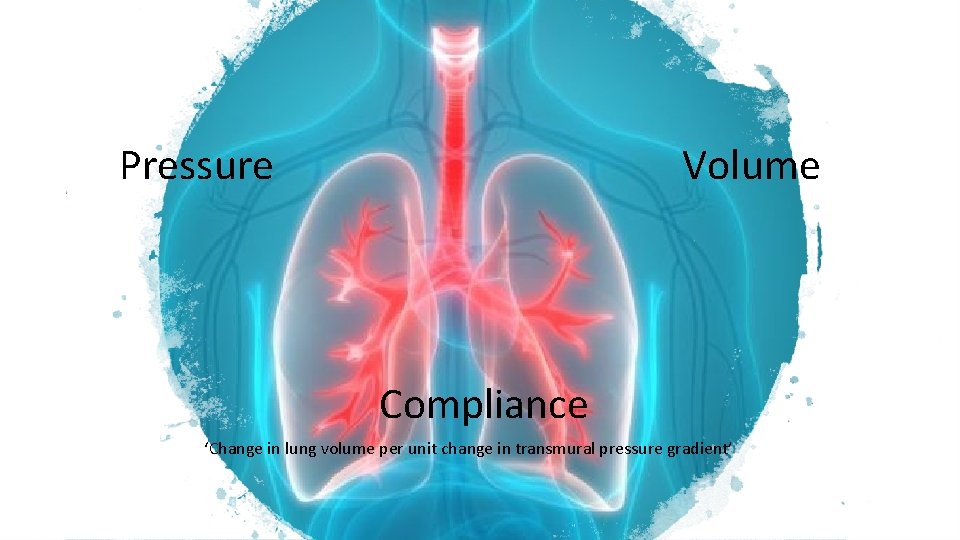

Pressure Volume Compliance ‘Change in lung volume per unit change in transmural pressure gradient’